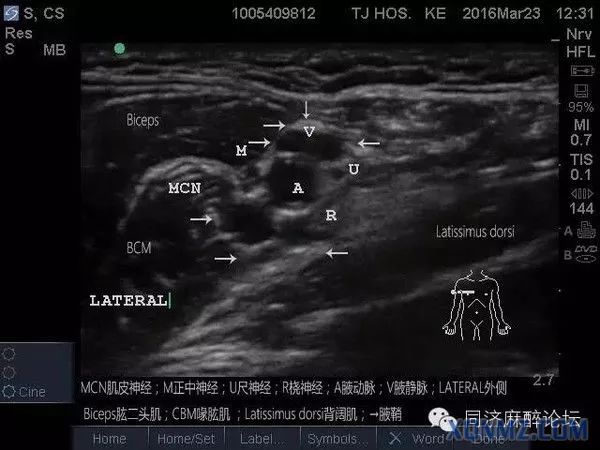

超声下肌间沟水平臂丛的走行图像,上面是胸锁乳突肌,左右是前、中斜角肌。肌间沟水平下可清楚看到呈串珠样的臂丛,C5、C6、C7等。请大家关注下,有的时候能看见5个“串珠”,不要以为是臂丛的5个根即C5、C6、C7、C8、T1,肌间沟往往是在颈椎7水平,怎么可能看到C8、T1,其实就是C5、C6、C7,那为什么是5个“串珠”?因为C6及C7在肌间沟水平已经分出2根,要避免在这2根汇合处之间穿刺而造成C6及C7的神经损伤。

超声引导穿刺针逐渐接触臂丛神经图像

超声引导穿刺针刺入臂丛神经外膜

女患35岁,腕部肿物,做超声引导下腋路臂丛阻滞。

从解剖上看切口皮肤支配的神经是前臂内侧皮神经,而前臂内侧皮神经在腋窝的走行是腋动脉及腋静脉之间,所以超声下穿刺在进入腋动脉及腋静脉之间时,发现神经电刺激仪0.3就出现该区域皮肤震颤,给予局麻药5-10ml就可把手术做下来。